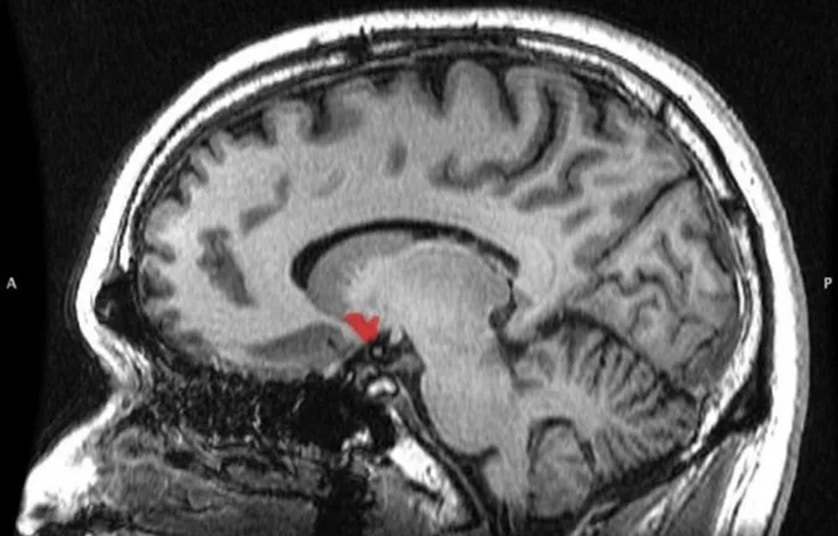

Bu taajjublanarli emas: inson hayot tarzi faqat bir necha asr oldin keskin o‘zgardi, butun evolyutsiya miqyosida esa bu juda qisqa muddat — shuning uchun miyamiz hali moslasha olmayapti. Bu impulsiv xarid qilish mexanizmini miyamizning uchta qismi boshqaradi: yonma-yon joylashgan yadro, bodomsimon tana va orbitofrontal po‘stloq.

Bu qanday ishlashi quyidagicha: biz ajoyib, mazali yoki chiroyli narsani ko‘rganimizda, yondosh yadro faollashadi va bizga: «Kel, buni sotib olaylik, chunki uni xohlaymiz», deydi. Shu paytda bodomsimon tana ishga tushib: «Ha, juda zo‘r, lekin agar buni hozir sotib olsak, kommunal to‘lovlar uchun pulimiz yetmay qoladi va qarzga botamiz», deydi. Shundan so‘ng, orbitofrontal po‘stloq vaziyatni tahlil qilib, kim haqligini aniqlaydi — yondosh yadro yoki bodomsimon tana va bizga sotib olishga ruxsat beradi yoki taqiqlaydi.

Demak, ushbu sxemada yondosh yadroning vazifasi — vasvasaga solish, bodomsimon tananing vazifasi — xarid qilishdan voz kechishning oqilona sabablarini topish, orbitofrontal po‘stloqning vazifasi esa — hozir qanday katta lazzat olishimiz va buning uchun kelajakda qanday dahshatli oqibatlar kutayotganini hisobga olib, «hukm» chiqarishdir.